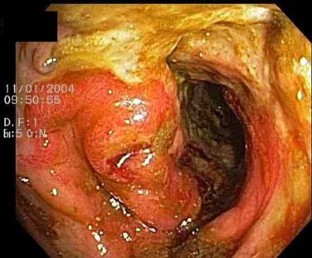

Fig. 2